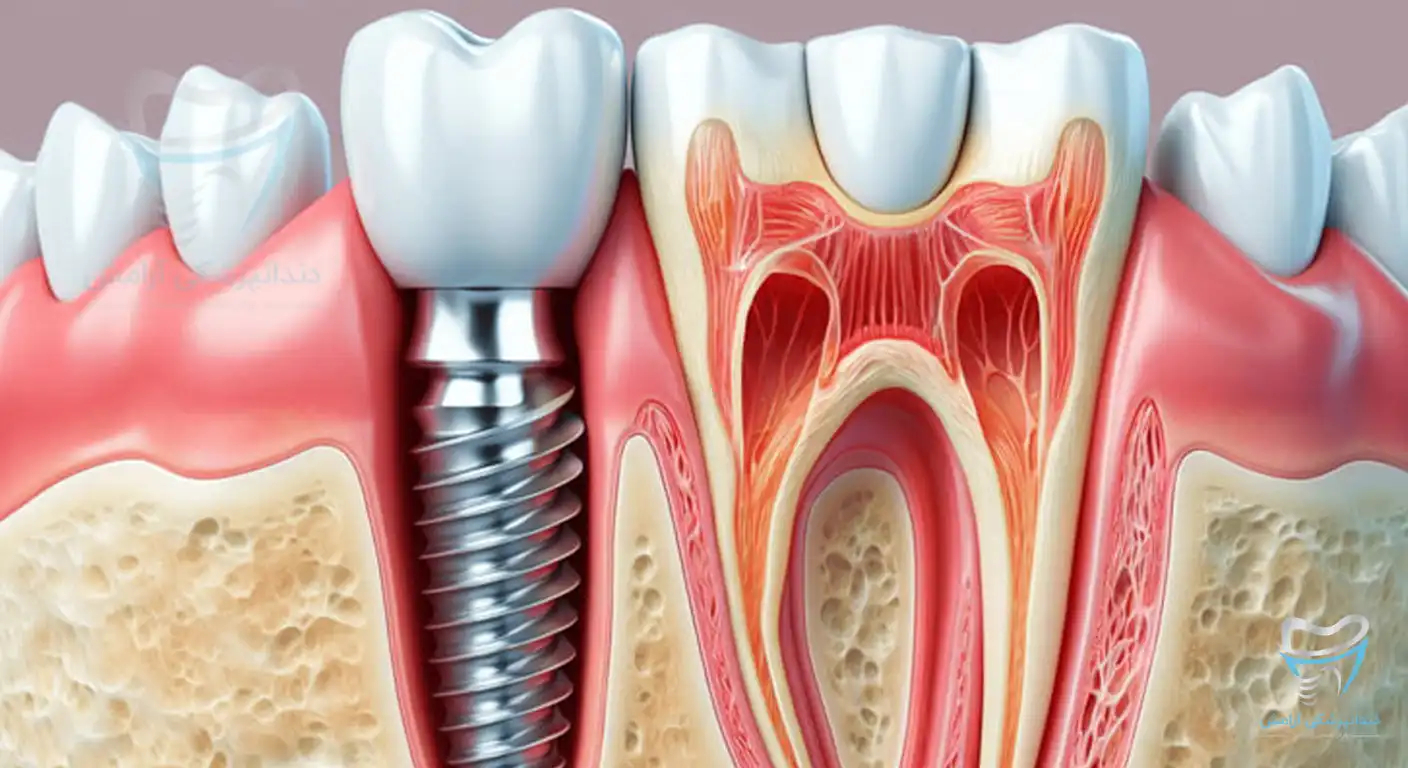

ایمپلنت دندان ازجمله پیشرفتهترین روشها برای جایگزینی دندانهای از دست رفته است. در این روش پایههای فلزی در استخوان فک قرار داده میشوند و امکان تثبیت دندانهای مصنوعی فراهم میگردد. این روش درمانی برای افرادی مناسب است که به دنبال راهکار دائمی برای جایگزینی دندانهای خود هستند.

ایمپلنت دندان مصنوعی میتواند به عنوان یک راهکار دائمی برای جایگزینی دندانهای از دست رفته بهکار برود. در این روش پایههای فلزی در استخوان فک قرار میگیرند و بهعنوان ریشه دندان عمل میکنند. تاجهای دندانهای مصنوعی روی این پایهها قرار گرفته و دندانهایی شبیه دندان طبیعی به وجود میآید. ایمپلنت دندان مصنوعی با دارا بودن ثبات بیشتر و بهبود عملکرد در جویدن، از تحلیل رفتن استخوانهای فک جلوگیری میکند.

ایمپلنت دندان از بهترین روشهای درمانی برای جایگزینی دندانهای از دست رفته است. این روش به کمک پایههای فلزی از جنس تیتانیوم که در استخوان فک کاشته میشود، یک ریشه مصنوعی برای دندان جدید فراهم میکند. سپس تاج دندان ساخته شده از مواد مقاوم و طبیعی روی این پایه نصب میشود.

دندان ایمپلنت، روش پیشرفته و دائمی برای جایگزینی دندانهای از دست رفته است. در روش ایمپلنت دندان یک پایه فلزی در استخوان فک قرار میگیرد. این پایه نقش ریشه دندان طبیعی را ایفا میکند و پس از جوش خوردن با استخوان میتواند تاج مصنوعی دندان را روی خود حمل کند. دندان ایمپلنت عملکرد و ظاهری مشابه دندان طبیعی دارد.